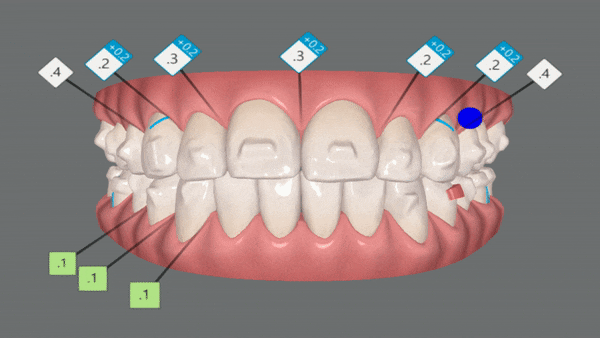

클린체크를 통해 어떻게 변화했는지 같이 확인해보실게요~!

인비절라인은 치아이동 시뮬레이션을 클린체크를 통해 확인 해 볼 수 있는것이 인비절라인 장점중의 하나 입니다.

클린체크란?

환자의 초기 임상 상태부터 치료를 마친 최종 교합상태까지 모든 치료 단계를 시뮬레이션하고, 치아의 미세한 움직임까지 3D 컨트롤 할 수 있는 디지털 플랫폼 입니다. -출처: 인비절라인-

첫번째 클린체크

1st Clincheck

총 29개의 인비절라인 장치로 클린체크대로 마무리가 되었습니다.

오른쪽 클린체크를 보시면 어금니들이 뒤로 이동하면서 동시에 함입이 됩니다.

인비절라인은 특수 강화 플라스틱 장치로 치아를 안쪽 , 바깥쪽에서 잡아주기 때문에 어금니 함입과 동시에 치아 배열이 가능합니다. 불필요한 치아이동이 없기때문에 기간이 단축 될 수 있는 장점이 있습니다.